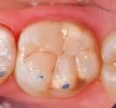

Some microdentistry and an amalgam replacement for this lovely man. No need for any shade selection in particular, this one matches everything =)